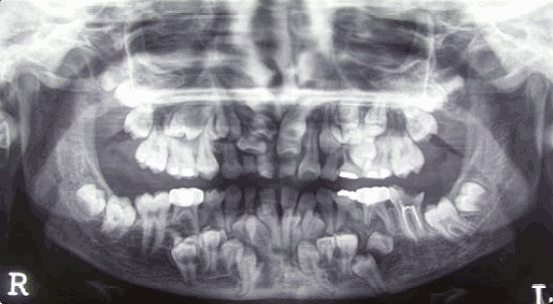

Cleidocranial Dysplasia

Oral complications of cleidocranial dysplasia

Prolonged retention of deciduous teeth

Delayed or failure of eruption of permanent teeth

Numerous unerupted permanent and supernumerary teeth